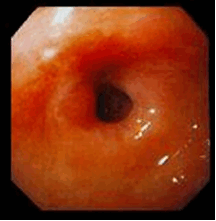

Рис.3. Малигнизация язвы желудка

Рис.4. Стеноз привратника

Стеноз привратника и двенадцатиперстной кишки

Иначе называется «непроходимость пилорического отдела желудка», затруднение прохождения пищи из желудка в кишечник в результате деформации или сужения места перехода желудка в 12-перстную кишку. Возникает в результате рубцевания язвы, расположенной в конечном отделе желудка или начальном отделе 12-перстной кишки.

Незначительная степень сужения привратника проявляется тяжестью в верхней половине живота в течение нескольких часов после еды, отрыжкой кислым, периодической рвотой съеденной пищей, приносящей облегчение.

По мере прогрессирования этого состояния происходит постоянная задержка части пищи в желудке и его перерастяжение, появляется гнилостный запах изо рта, отрыжка тухлым, больные жалуются на интенсивную боль в животе, постоянную рвоту пищей. Нарушение пищеварения со временем приводит к истощению и обезвоживанию больного.